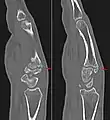

Carpal boss in plain X-Ray.